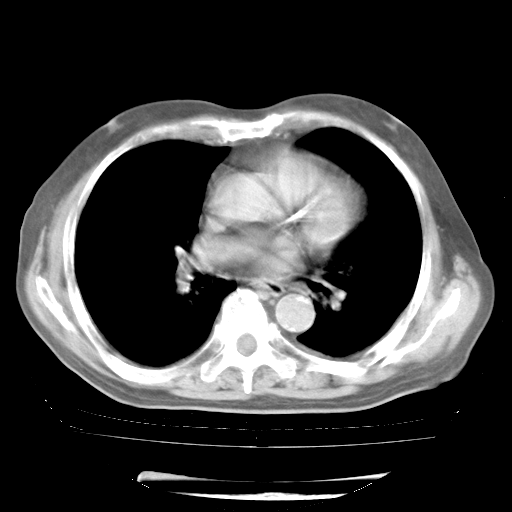

4月28日肺部CT——再次出现类似去年5月9日——透光度降低,“间质性”改变。